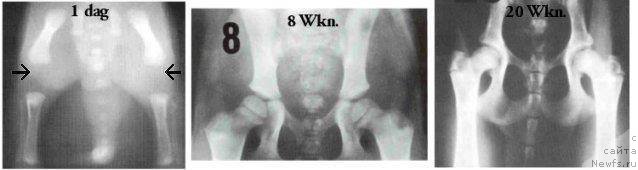

На этих фотографиях можно увидеть с какими суставами щенки рождаютя и как раз идет дальнейшее развитие суставов.

Снимки сделаны в возрасте 1 дня, 8 недель и 20 недель.

Глядя на эти снимки поимаешь, как важно правильное выращивание собаки и как опасны даже небольшие травмы для маленького щенка.

И я думаю, что глядя на эти снимки становится очень поняно, как важны первые 6 месяцев в жизни щенка. И как важны правильное питание правильный режим прогулок.